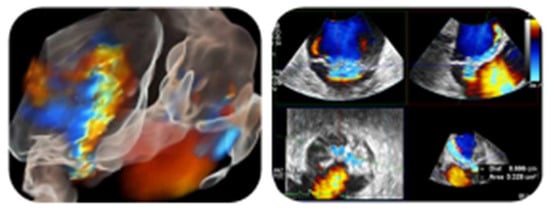

- The fundamental role of multimodality imaging (TTE + TEE, brain MRI, 18F-FDG/PET–CT scan) for NBTE diagnosis;

- The role of 2D and 3D-TEE for detection and characterization of NBTE valvular lesions;